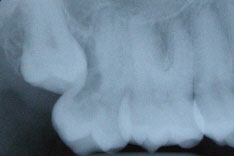

На этом рентгеновском снимке видны, в первую очередь, «пустые» корневые каналы и довольно больших размеров очаг воспаления (то, что часто называют гранулемой, кистой) на верхушке одного из корней. В общем итоге в одном зубе был сконцентрирован целый букет ошибок и недоделок, одним словом, это образец недобросовестной работы стоматолога. Я стараюсь о коллегах всегда говорить или хорошо или молчать, но в данном случае надо смотреть правде в глаза – зуб загублен именно стоматологом. Никаких объективных сложностей для качественной работы изначально здесь не было. Зато появились теперь. Прогноз на будущее для таких зубов всегда строится, исходя из 2 основных проблем – насколько приведет к успеху повторное лечение каналов и насколько будет успешной попытка адекватного восстановления зуба после этого. Оценив вероятность долговременного успеха этих двух составляющих, можно решать, стоит ли «спасать» зуб от щипцов хирурга. Ведь, в любом случае, лечение стоит денег, а гарантировать результат здесь невозможно. Можно только предполагать вероятность успеха. В данном случае каналы не выглядели непроходимыми. Да и восстановить зуб коронкой, даже несмотря на большую степень разрушения, все еще представлялось возможным. А потому было принято решение о начале лечения.